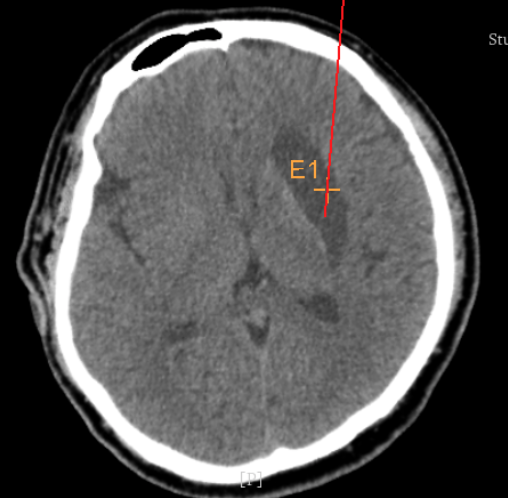

手術(shù)日當(dāng)天,醫(yī)生團(tuán)隊(duì)通過手術(shù)計(jì)劃系統(tǒng)為患者制定手術(shù)靶點(diǎn)及最安全的入顱路徑,隨后將手術(shù)規(guī)劃導(dǎo)入手術(shù)室的機(jī)器人當(dāng)中。

實(shí)際手術(shù)時(shí),機(jī)器人在幾分鐘內(nèi)就完成了空間注冊,機(jī)械臂在定位儀的引導(dǎo)下自動定位,準(zhǔn)確鎖定靶點(diǎn)。